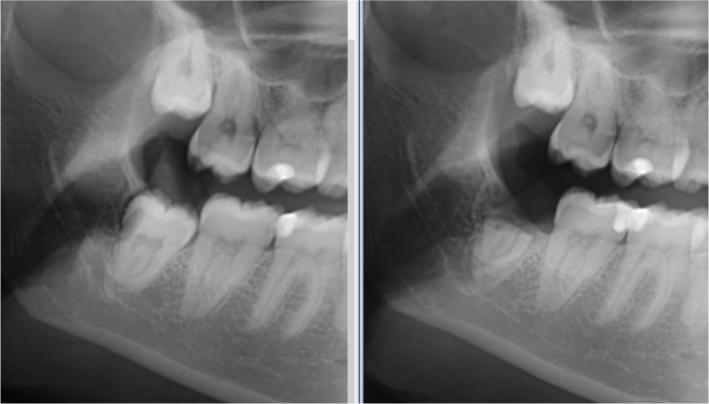

下颌第三磨牙(3M)通常与病理相关,需要手术切除。3M的移除会造成下牙槽神经(IAN)的损伤。冠状切除术是3M的一种手术选择,对IAN有很大的损伤风险,只有冠被移除,根/根留在原位,手术后可能会移动。方法:回顾性分析2014年至2020年在卑尔根大学临床齿科研究所口腔颌面外科诊所(IKO)进行的冠状切除术的结果。在此期间,共进行了63例冠状切除术。经区域伦理委员会批准,我们联系了所有63例患者,共有44例患者同意参加本研究。基于全景x线片(OPG)进行放射学分析,并分析患者记录,以评估哪些人口统计学和当地因素与根迁移以及术后并发症的数量有关。结果:牙根迁移与性别、牙根解剖结构或牙嵌塞模式无关。牙根迁移在年龄较小(即≤25岁)的人群中更为常见。术后并发症4例;其中两例通过全身抗生素治疗,而另外两例则需要手术干预以去除剩余的根。没有短暂或永久性神经感觉障碍的病例报告。结论:冠状切除术是避免3M切除神经损伤的可行方法。

Mandibular third molars (3M) are often associated with pathologies necessitating their surgical removal. Removal of 3M can cause injury to the inferior alveolar nerve (IAN). In coronectomy, a surgical option for 3M that present a significant risk of injury to the IAN, only the crown is removed, and the root/roots are left in situ, and may move after surgery. Methodology: A retrospective review was done to analyse the outcomes of coronectomy procedures performed at the Clinic of Oral and Maxillofacial Surgery, Institute of Clinical Odontology (IKO), University of Bergen (UiB) between 2014 and 2020. During this period, a total of 63 coronectomy procedures were performed. All 63 patients were contacted after approval from the regional ethical committee, and a total of 44 patients consented to participate in the study. Radiographic analysis was done based on panoramic radiographs (OPG), and patient records were analysed to assess which demographic and local factors were associated with root migration along with the number of post-operative complications. Results: Root migration was not associated with gender, root anatomy, or pattern of tooth impaction. Root migration was observed significantly more often in the younger age group, that is, ≤25 years. There were four reported cases of post-operative complications; two of those cases resolved with systemic antibiotics, while surgical intervention was necessary in the other two cases to remove the remaining roots. There were no reported cases of transient or permanent neurosensory disturbances.  Conclusion: Coronectomy is a viable technique to avoid nerve injury with 3M removal.